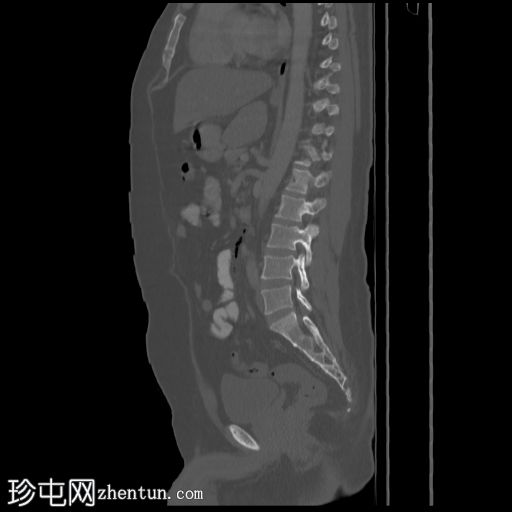

矢状位骨窗

降结肠和乙状结肠可见多个小憩室,伴有少量小(亚厘米级)区域淋巴结肿大。周围脂肪和肠壁无明显增厚。

远端降结肠后壁可见一小(<15 mm)、局限性空腔,内含气泡,伴有不规则肠壁强化和轻度邻近肠系膜脂肪条索状改变。

未见脓肿、腹水、弥漫性气腹,提示IA期复杂性急性穿孔性憩室炎(局部穿孔)。